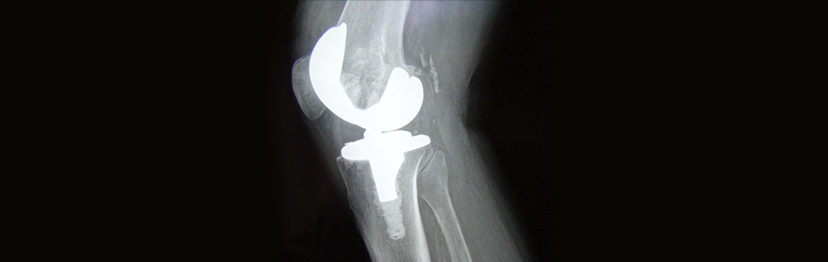

Reines Titan und Titanlegierungen können auch zu künstlichen Gelenken und medizinischen Geräten verarbeitet werden.